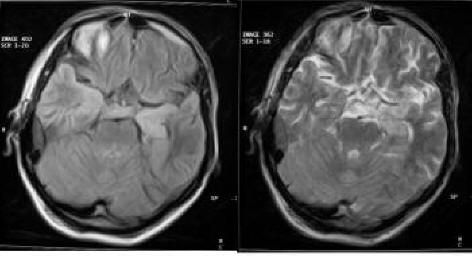

Case Report Neurosyphilis Presenting With Dementia, Chronic ...

Case report Open Access Neurosyphilis presenting with dementia, chronic chorioretinitis and adverse reactions to treatment: a case report Shima Mehrabian1*, Margarita Radoslavova Raycheva1, ... Document Viewer